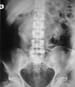

Retrograde ureterogram in a patient with retroperitoneal fibrosis reveals smooth narrowing and medial shift of the ureter.